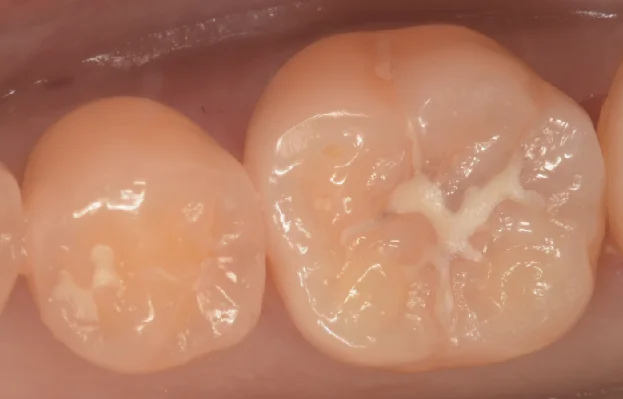

昔の保険治療部位を最小限の削合で再修復

20代女性(群馬県前橋市から来院)の左下6番に、旧CRの欠けと裂溝最深部からの二次う蝕。短時間ケース方針として最初からラバーダム防湿下で、健全歯質を最大限温存して1回約45分でダイレクトボンディング再修復しました。